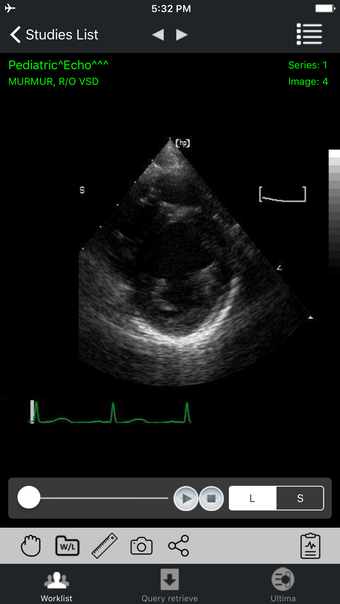

iPaxera là một ứng dụng xem PACS thân thiện với người dùng được thiết kế cho các thiết bị iOS, cung cấp việc điều hướng mượt mà của hình ảnh DICOM. Nó cho phép thêm các nghiên cứu từ PC, đĩa CD DICOM hoặc bộ nhớ flash trực tiếp vào iPhone hoặc iPad của bạn thông qua đồng bộ hóa iTunes. iPaxera tự hào về giao diện trực tiếp với PaxeraView, nâng cao khả năng xem chẩn đoán. Ứng dụng có một công cụ báo cáo nhúng để viết báo cáo, gửi email hoặc lưu báo cáo cùng với nghiên cứu. Người dùng có thể tận dụng công cụ nhận dạng giọng nói chung để đọc. iPaxera hỗ trợ DICOM Cine với các điều khiển phát lại tương tác, đặc biệt hữu ích cho các nghiên cứu về Cardiac Cath và Echo. Với một danh sách công việc tương tác, tiêu chí tìm kiếm cụ thể và thông tin nghiên cứu cần thiết, iPaxera đảm bảo quản lý nghiên cứu và trực quan hóa dễ dàng.

Các tính năng chính bao gồm đồng bộ hóa nghiên cứu qua iTunes, một công cụ báo cáo trực quan, điều hướng hình ảnh tương tác, phóng to, di chuyển, xoay và đo khoảng cách. Người dùng có thể điều chỉnh chiều rộng cửa sổ và mức với cử chỉ đơn giản và đặt lại hình ảnh bằng cách nhấp đôi.